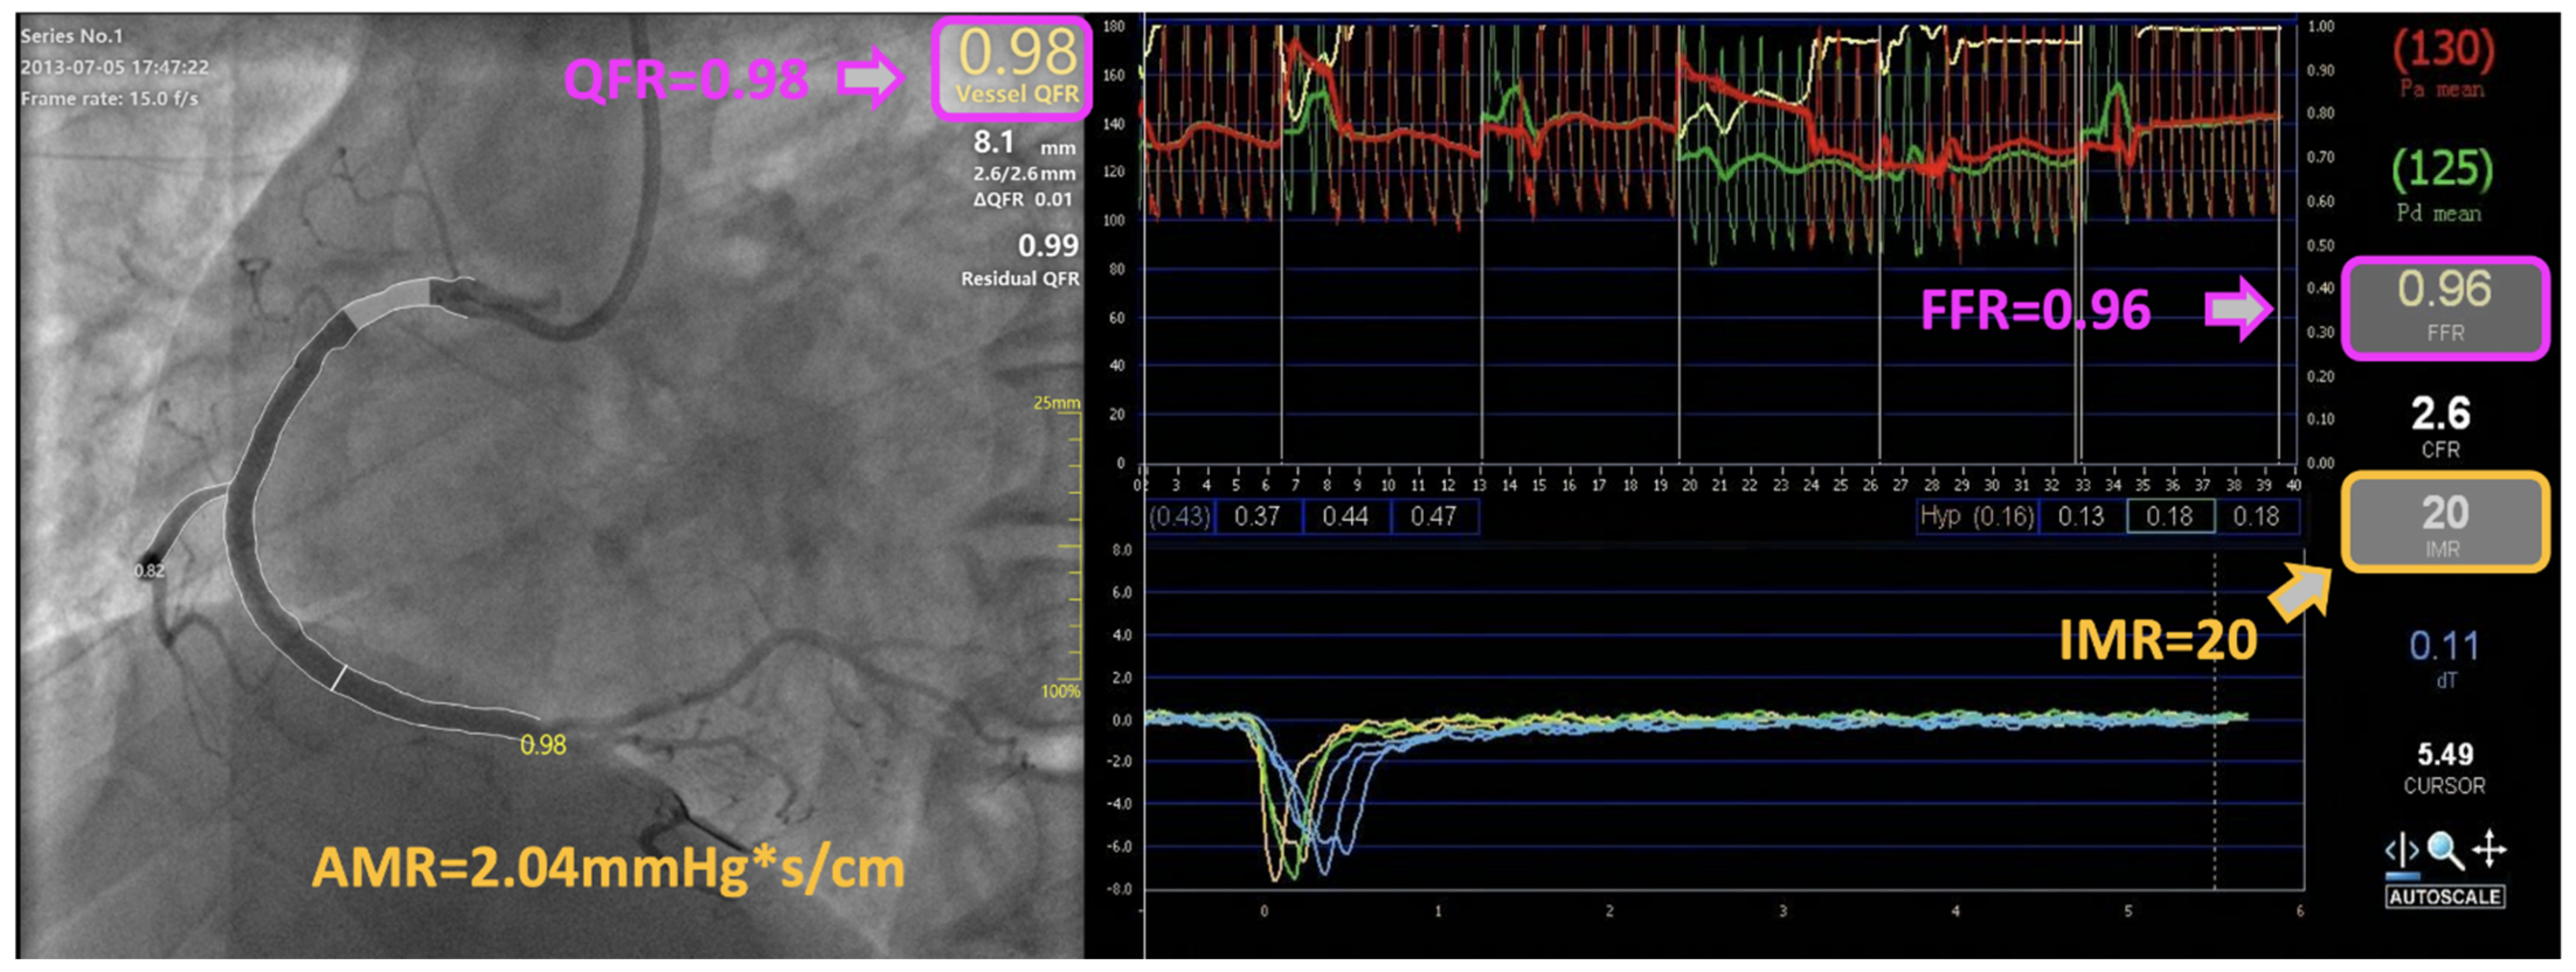

To conclude, AMR is a novel angiography-derived index that aims at increasing the availability of a prompt and integrated assessment of the microvascular function. This might represent a major step forward towards precision medicine implementation, with improvement in the diagnostic and therapeutic pathway of all the patients referred for invasive angiography assessment, over a wide span of clinical settings. Interestingly, according to our analysis, this approach led to the detection of a high CMD rate, even in patients with CCS in whom high MR was not anticipated from clinical variables. Therefore, the use of angiography-based computational technologies offers the net advantage of a systematic and comprehensive physiological assessment of both epicardial and microvascular determinants of the coronary circulation, in a fast, simple, and reproducible manner. A comprehensive illustration of the integrated coronary physiological computation based on single-view coronary angiography is provided in Figure 5.

Figure 5.

Derivation of coronary microvascular resistance from coronary angiography. An illustrative case-example of integrated angiography-derived epicardial and microvascular physiology assessment in a patient presenting with unstable angina: values of the pressure-wire thermodilution-derived index of microvascular resistance (IMR) and angio-derived microcirculatory resistance (AMR) index showed concordance and good agreement. AMR, angio-derived microcirculatory resistance; FFR, fractional flow reserve; IMR, index of microvascular resistance; QFR, quantitative flow ratio.